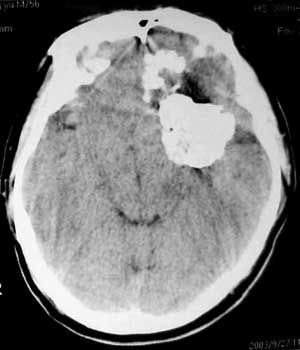

男性,60岁,反复癜痫40余年。

病理结果

骨软骨瘤